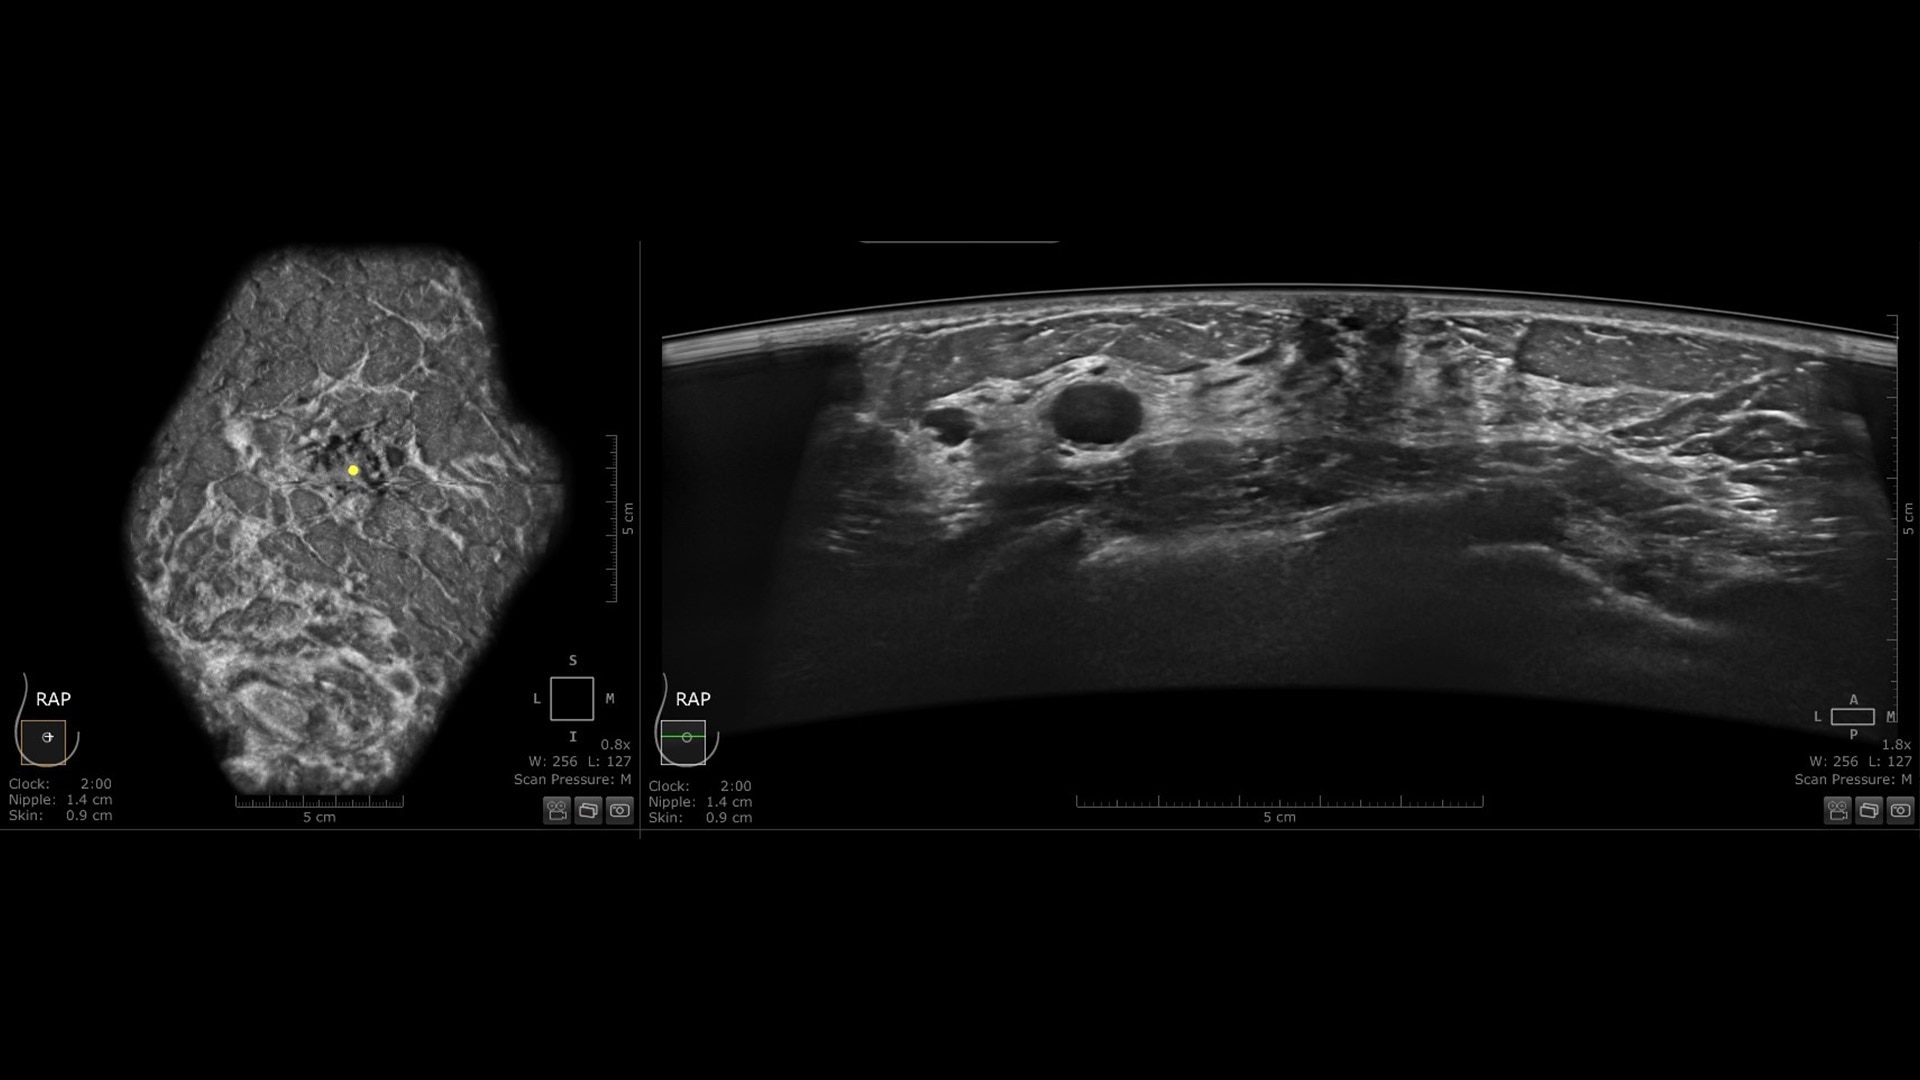

Dense breast tissue and cancer appear white on a mammogram, potentially camouflaging small cancers, and in fact, up to 50% of breast cancers may be missed in extremely dense breasts.⁴

The Invenia ABUS Premium is designed for high patient throughput and extraordinary image quality to provide a great level of confidence. With its innovative design, it’s easy to use, reproducible, user-independent, standardized and allows reading anywhere.

The novel Reverse Curve™ transducer is designed for enhanced performance

Its gentle 15.3 cm shape follows the breast's natural contour, enhancing patient comfort* and ensuring full contact for comprehensive coverage. The improved image quality* increases diagnostic confidence for reading ABUS exams.

Excellent image quality and 40% faster scan speed

• cSound Imageformer, software-based processing, produces exquisite, reproducible images by leveraging automatic focus at every pixel.

• Fast Scan increases scan speed by 40%*, fostering improved efficiency and patient throughput.

Centralized reading everywhere with the Invenia ABUS Viewer with AI Assistant

Invenia ABUS Viewer’s efficient workflow, with AI Assistant**, allows physicians to quickly review, interpret, and archive exams, even remotely.

• Decrease benign biopsies by up to 55% with Koios DS™ Breast